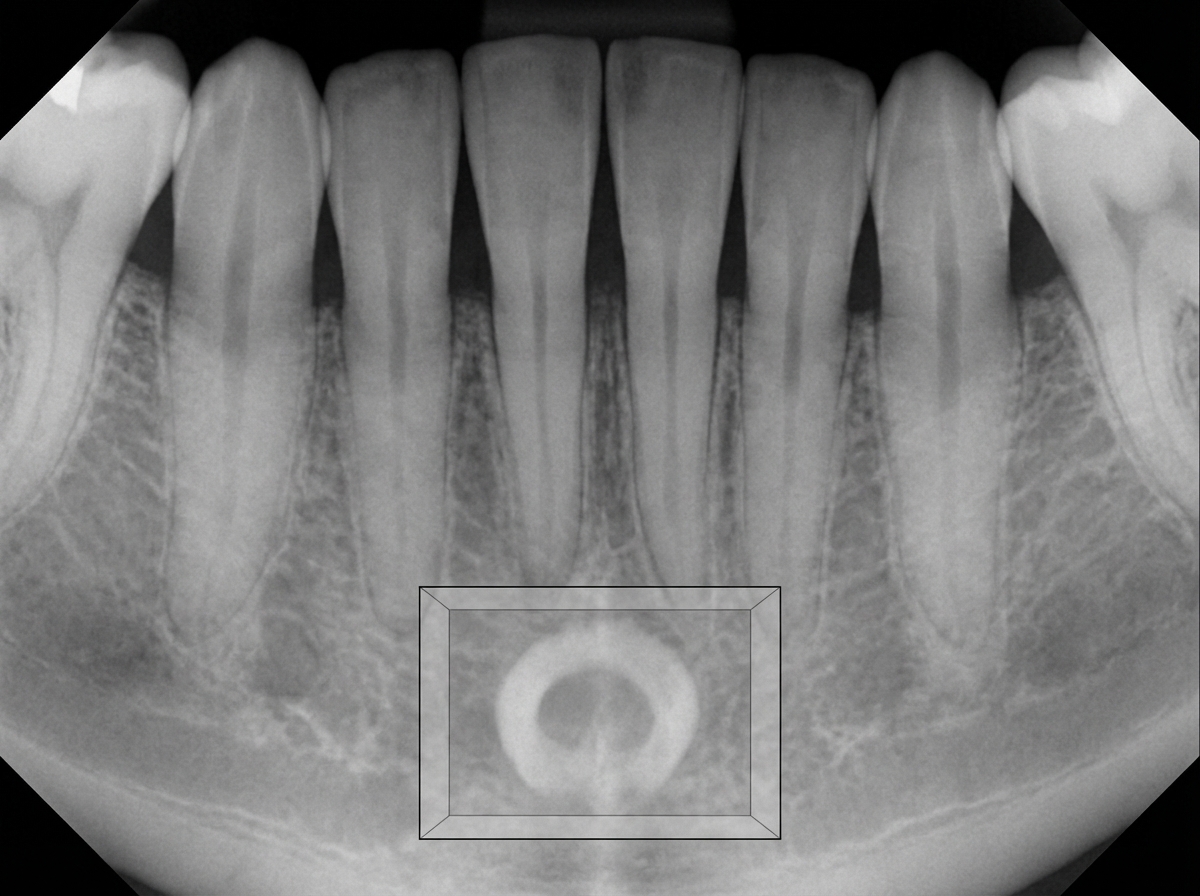

The radiopaque structure shown in the box is most likely:

Explanation: ***Genial tubercle*** - The **genial tubercle** appears as a **radiopaque structure** on dental radiographs due to its bony composition and serves as attachment point for **genioglossus** and **geniohyoid muscles**. - Located at the **lingual surface** of the mandibular symphysis, it creates a characteristic **dense radiopaque shadow** on periapical and panoramic radiographs. *Lingual foramen* - The **lingual foramen** appears as a **radiolucent (dark) area**, not radiopaque, as it represents a **canal or opening** in the bone. - Located **below the genial tubercle**, it allows passage of the **lingual artery** and appears as a small circular radiolucency. *PCD* - **Periapical cemento-osseous dysplasia (PCD)** typically affects the **periapical regions** of anterior teeth, not the symphyseal area. - It shows **mixed radiolucent-radiopaque patterns** around tooth roots, not a single radiopaque mass in the symphysis. *None of the above* - This option is incorrect as the **genial tubercle** is the most appropriate answer for a radiopaque structure in this anatomical location. - The radiographic appearance and location are **pathognomonic** for genial tubercle on mandibular radiographs.